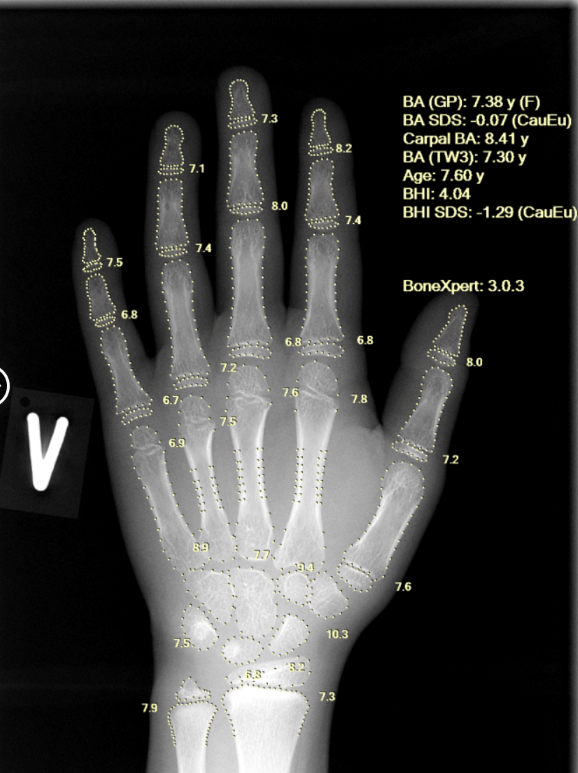

Aarthi Scans & Labs Rolls Out AI-Based Bone Age Technology across 100 Centres in India

Developed by a Europe-based AI med-tech company and CE-approved, BoneXpert is considered a gold-standard solution for automated bone age assessment...